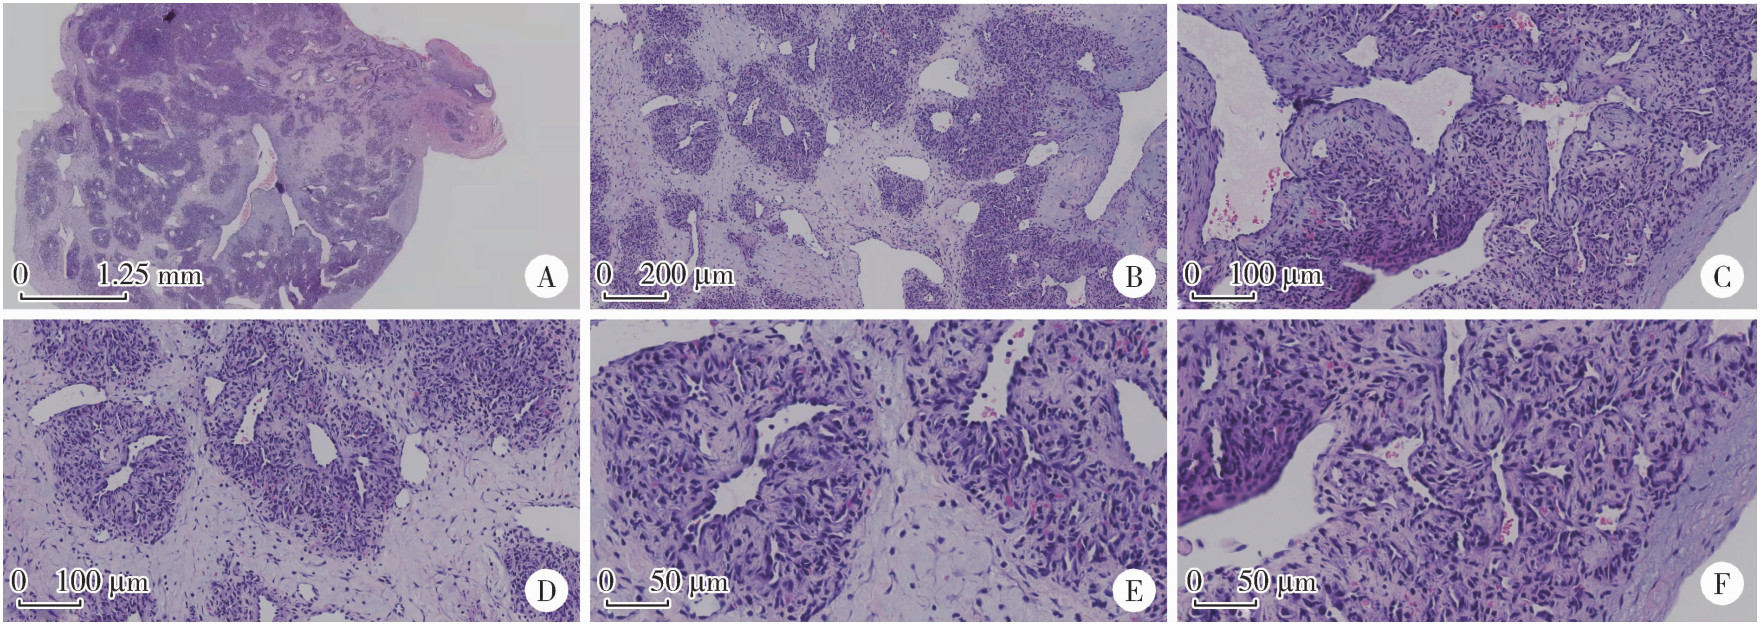

患者为男性,36岁,主因左颈部皮下肿物入院。患者1个月前无明显诱因发现左颈中部皮下一约黄豆大小肿物,于外院就诊时超声检查提示IPEH可能。随后患者于北京大学第三医院门诊就诊,以“左颈部IPEH待查”收入院。既往肾结石病史。查体:左颈部胸锁乳突肌中上段皮下扪及一约黄豆大小肿物,质韧,边界清,可活动,无红肿及压痛,表面无破溃,体位试验阴性,未闻及血管杂音。术前常规实验室检查均正常。彩色多普勒超声提示,左侧颈外触及肿物处局部浅静脉内可见一低回声实性结节,大小约0.8 cm×0.5 cm×1.0 cm,边界清,不可压缩,病灶内可见丰富血流信号,并可探及低频阻动脉频谱,峰值血流速度为38 cm/s,病变两端浅静脉管腔均可压,诊断为IPEH可能(图 1)。

图1 IPEH患者的超声影像

Figure 1 Ultrasound imaging of the patient with IPEH

A, a hypoechoic nodule with clear, incompressible borders was seen in a local superficial vein; B, color doppler imageing shows rich blood flow signal; C, adjacency of the nodule to the surrounding neck vessels.IPEH, intravascular papillary endothelial hyperplasia.